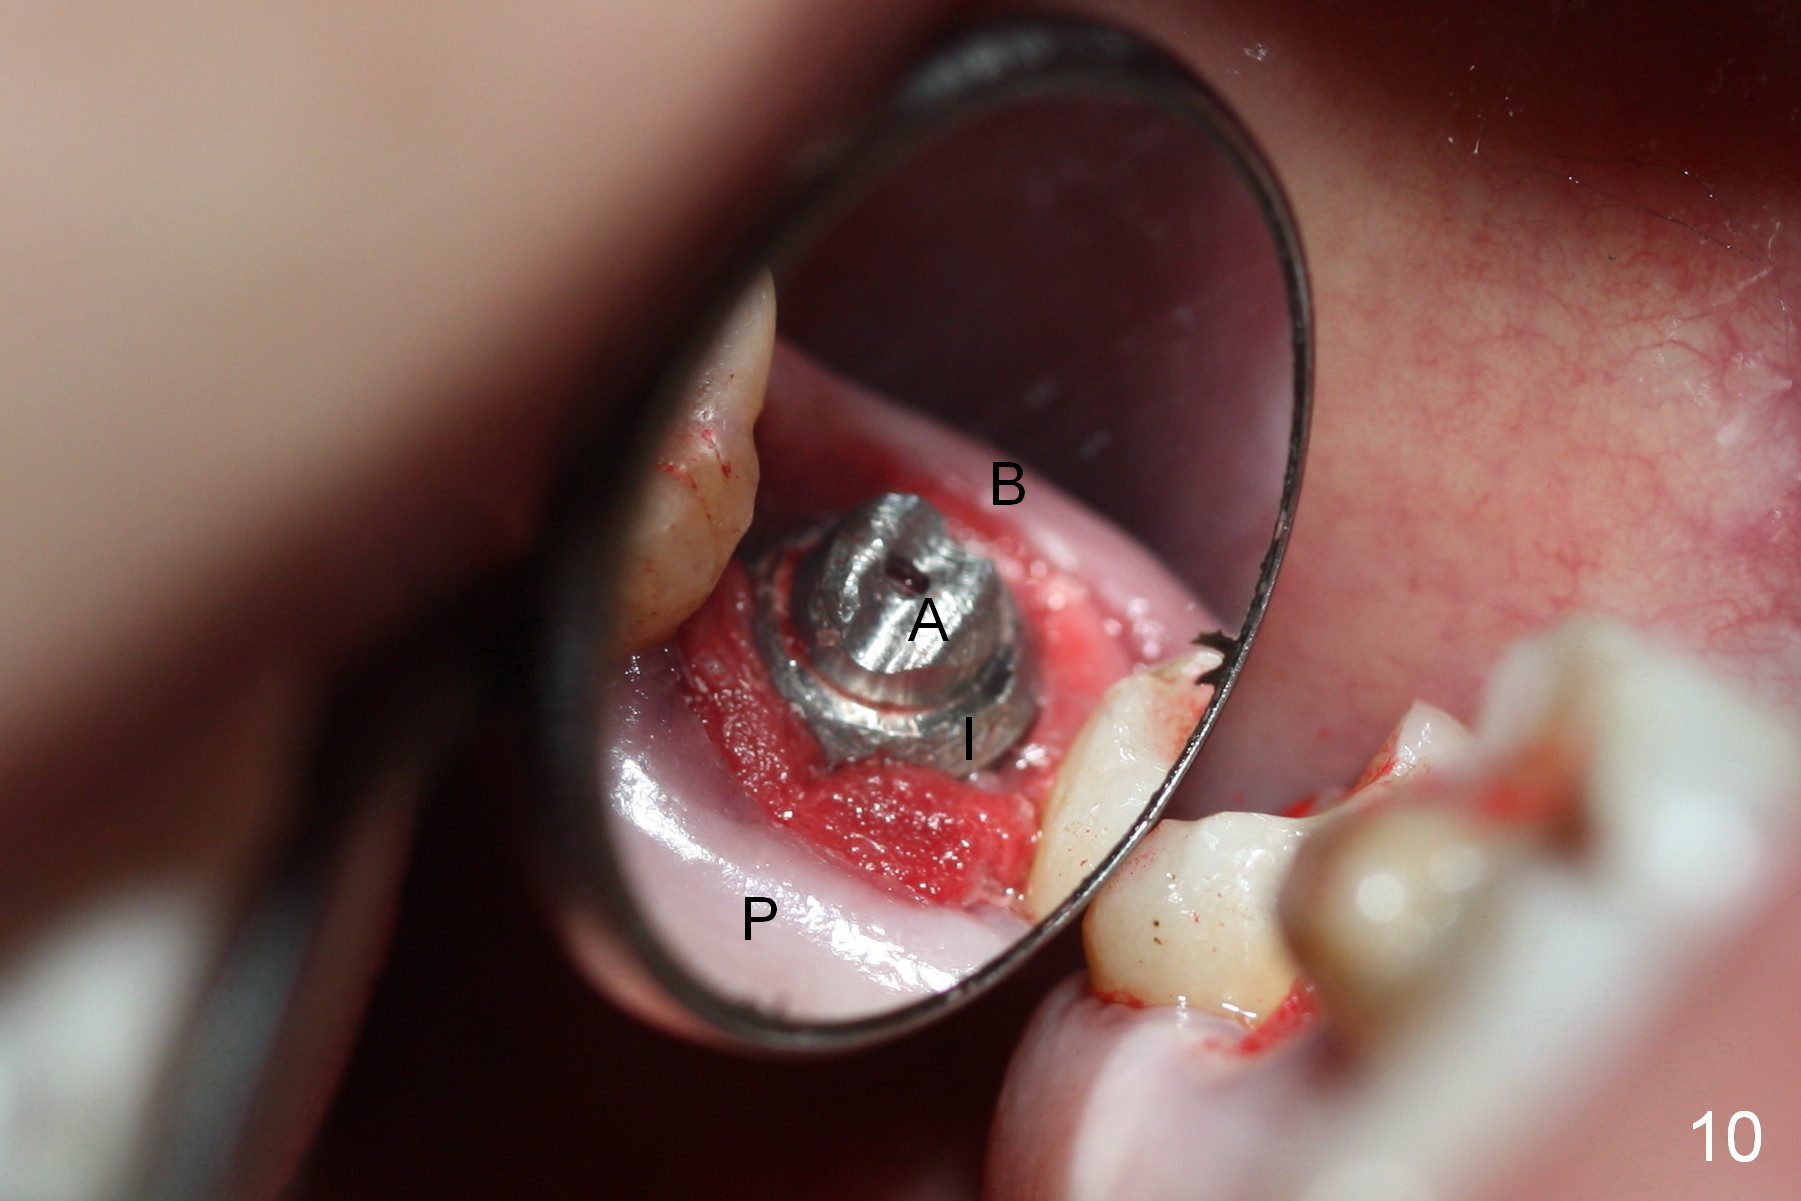

Osteotomy for immediate implant is initiated with a 2 mm pilot drill (Fig.6b red arrow) in the coronal end of the buccal slope of the septum (center of the socket). Once the drill gets initial penetration, the trajectory changes to the long axis of the tooth (Fig.6c). Then PA is taken with a parallel pin (Fig.7). It appears that the depth is not enough; there is bone apical to the pin. As osteotomy increases in diameter, burs may be deviated buccally due to the septal buccal slope (to be discussed below). With longer osteotomy, the deviation may be less. Osteotomy is deepened (Fig.6d). From this moment on, nose blowing test is done after each step. The result is all negative. As drill diameter increases, they do deviate buccally (Fig.6e arrow), since there is less bone contact buccally than lingually (compare Fig.6e,f). With the same reason, smaller tapered taps (Fig.6g pink, 5 and 6 mm) tend to be mobile buccally (arrow). When a large tap (7 mm) is inserted (Fig.8), there is no buccal mobility. It appears that the tap contacts more of the buccal plate (Fig.6h), but the coronal end of the tap is buccal (Fig.6i, pink circle). At each step of osteotomy, the coronal end of a bur or tap should be pushed as lingual as possible so that the final tap is favorable for restoration (Fig.6j). Sinus lift is done (Fig.6k red circle; Fig.9 *) before placement of 7x17 mm implant (I, >60 Ncm). Since the palatal socket is not associated with implant stability, it is closed by collagen plug (Fig.6l, blue area). As extra precaution, bone graft is placed around the coronal portion of the tissue-level implant (Fig.6l red circles), followed by collagen dressing.

Probably due to bruxism, there is limited vertical restorative space. The margin is subgingival except buccal (Fig.10,11). An immediate provisional (Fig.12 P) appears to have to be fabricated to prevent soft tissue from covering the margin during osteointegration. It is our intention to make gingival envelop larger than the definitive crown cervix. It would be easier to remove a permanent cement later on for peri-implantitis prevention.